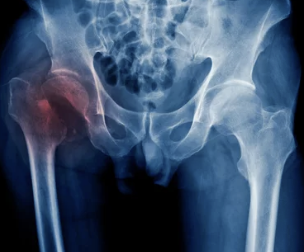

증상

- 고관절 통증: 움직일 때, 특히 걷거나 계단을 오를 때 통증이 심해질 수 있습니다.

- 뻣뻣함: 아침에 일어났을 때나 오래 앉아 있을 때 고관절이 뻣뻣할 수 있습니다.

- 움직임 제한: 고관절을 움직이는 범위가 제한될 수 있습니다.

- 발음: 걷거나 움직일 때 다리가 삐걱거리는 소리가 날 수 있습니다.

치료

- 초기 단계: 휴식, 혈액 순환 개선, 통증 완화

- 중증 단계: 관절 보존 수술 (고관절 재형술)

- 말기 단계: 인공 관절 수술